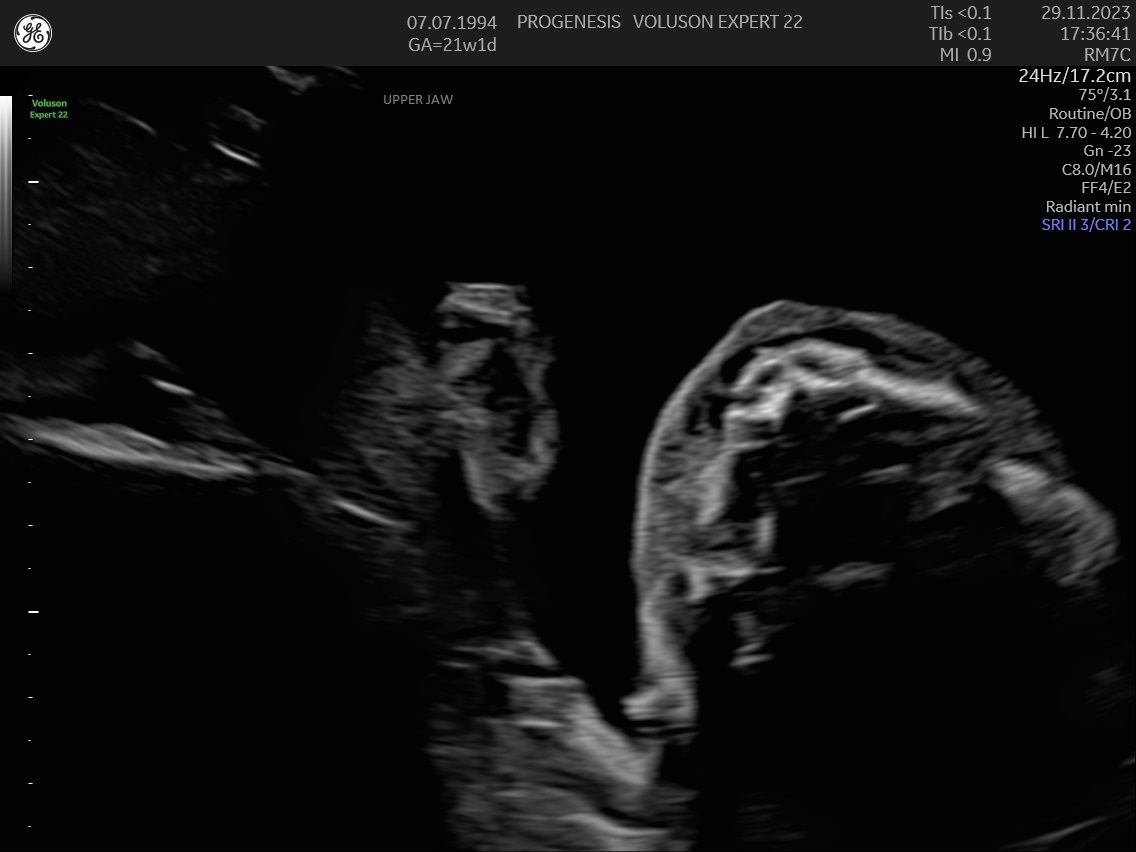

α) Η λεπτομερής αξιολόγηση της εμβρυϊκής ανατομίας, όπου αναγνωρίζονται τυχόν ανατομικές ανωμαλίες.